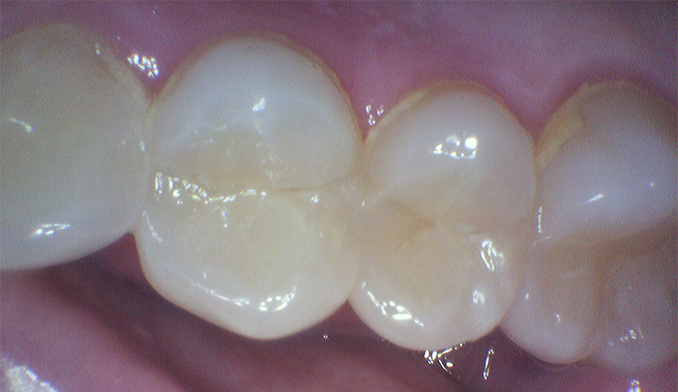

Same-Day Crown for Broken Molar

The patient broke a lower molar (second tooth from the back) while eating. Fortunately, the tooth was salvageable. We completed a same-day crown within two hours, restoring full strength and function.